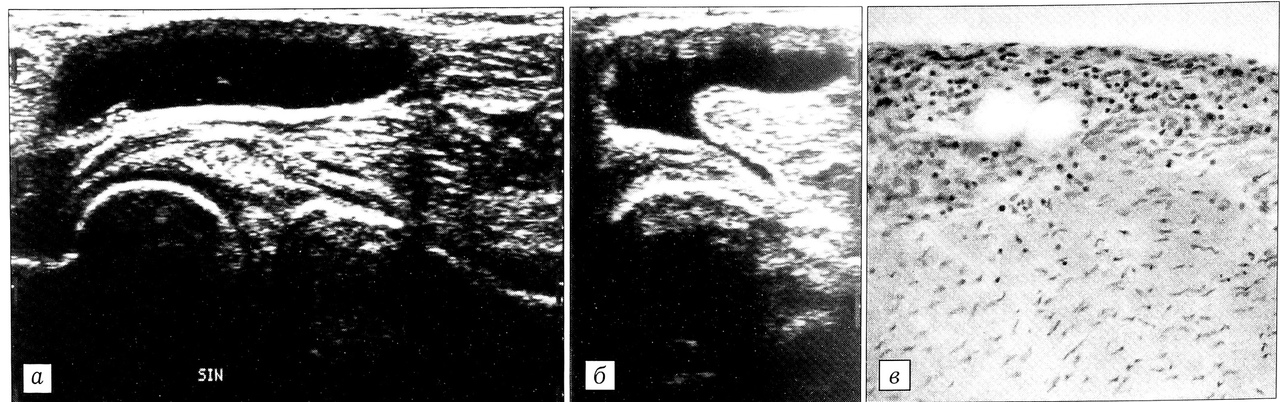

При давности патологического процесса 2,8±2,33 мес (р < 0,05) обследовано 5 больных с I рентгенологической стадией гонартроза (первая группа). На артросонограммах киста Бейкера визуализировалась как эхонегативное образование с четкими контурами. Синовиальная оболочка его была слабоэхогенна, незначительно утолщена — в пределах 1,5~2,5 мм (в среднем 1,96±0,04 мм). Содержимое анэхогенно. Четко определялась шейка кисты (рис. 1, а, б).

При гистологическом исследовании в стенке кисты выявлялись два слоя: внутренний (синовиальный), неравномерный по толщине, состоящий из пролиферирующей соединительной ткани, и глубокий слой, представленный плотной волокнистой соединительной тканью (рис. 1, в). Во внутреннем слое определялись в основном малодифференцированные соединительнотканные клетки и макрофагоциты. В глубоком слое отмечались скопления молодых фибробластов вокруг сосудов микроциркуляторного русла.

Таким образом, для данного периода формирования кисты характеры изменения эхоструктуры в виде незначительного (не превышающего 2,5 мм) утолщения синовиальной оболочки и анэхогенности содержимого без эховключений. При гистологическом исследовании обнаружены начальные проявления продуктивного воспаления в виде пролиферации клеток синовиального слоя, сопровождающейся его незначительным утолщением, и пролиферации адвентициальных клеток сосудов, расположенных в глубоком слое стенки кисты.

Указанные изменения структуры отнесены нами к раннему периоду пролиферативных изменений синовиальной кисты, которые могут подвергаться обратному развитию.

Рис. 1. Киста Бейкера, I период структурных изменений.а — с продольным, б — с поперечным сканированием: визуализируются незначительное (до 2,3 мм) утолщение синовиальной оболочки, анэхогенное содержимое (а), перешеек кисты (б); в — гистологическая картина стенки кисты: пролиферация соединительнотканных клеток внутреннего (синовиального) слоя (окраска гематоксилином и эозином, об. 16, ок. 10).